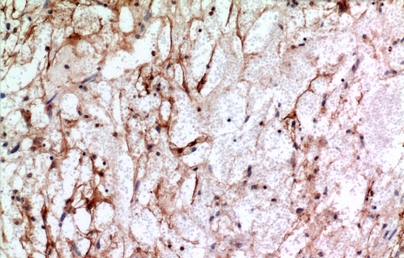

IHC (Immunohiostchemistry)

(Anti-IFITM1 antibody IHC of human uterus, endometrium. Immunohistochemistry of formalin-fixed, paraffin-embedded tissue after heat-induced antigen retrieval. Antibody concentration 5 ug/ml.)